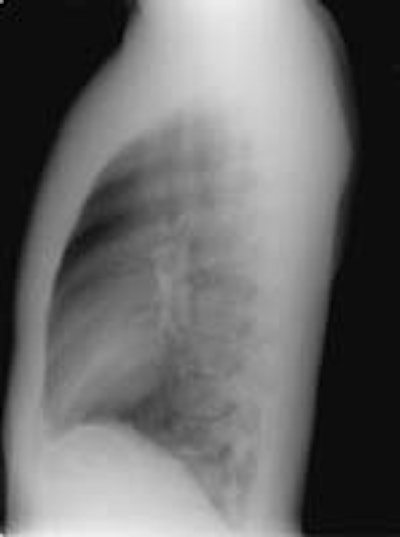

Alveolar Sarcoid:

The female patient shown in the images below presented with complaints of dyspnea on exertion. Although many disease processes were entertained in the differential for the findings on her exams, a transbronchial biopsy was performed and a diagnosis of sarcoid was made histologically.

The CXR revealed bilateral, large nodular opacities with poorly defined

margins: